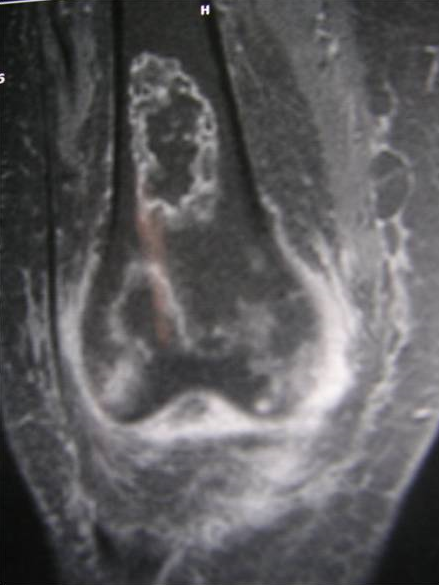

L'ostéonécrose des condyles fémoraux n'est pas rare au cours du lupus érythémateux systémique (LES), elle peut prendre le masque d'une arthrite septique ou favoriser celle 'ci. L'IRM est l'examen de référence pour un diagnostic précoce. Le mécanisme physiopathologique reste controversé, l'hypothèse d'une vascularite des vaisseaux épiphysaires n'a pas trouvé de confirmation anatomique. Néanmoins, plusieurs facteurs de risque ont été rapportés (corticothérapie, anticorps antiphospholipides). Nous rapportons l'observation d'une patiente âgée de 37ans suivie depuis 1995 pour un LES compliqué d'un purpura vasculaire et d'un syndrome quadripyramidal ayant bien évolué après administration de boli de solumédrol relayés par une corticothérapie orale. Neuf ans après le début de la maladie, la patiente développe une impotence fonctionnelle du membre inférieur droit. L'examen clinique, le bilan biologique et radiologique ont conclu à une arthrite subaigüe du genou droit. Plusieurs diagnostics étaient évoqués (arthrite inflammatoire dans le cadre d'une poussée de sa maladie, une arthrite septique ou une simple poussée d'arthrose). L'arthrite septique est le premier diagnostic à éliminer car elle met en jeu le pronostic fonctionnel et vital, elle a bénéficié d'une arthrotomie parapatellaire, des soins locaux et une antibiothérapie. Néanmoins devant l'installation subaigüe de la symptomatologie et tout en sachant que l'arthrite septique au cours de LES, survient exceptionnellement sans point d'appel articulaire et elle complique volontiers une articulation fragilisée on a demandé une IRM du genou qui a objectivé une abrasion du cartilage et de l'os sous chondral des deux condyles fémoraux au niveau de leur versant postérieur (stade B de Mitchell).